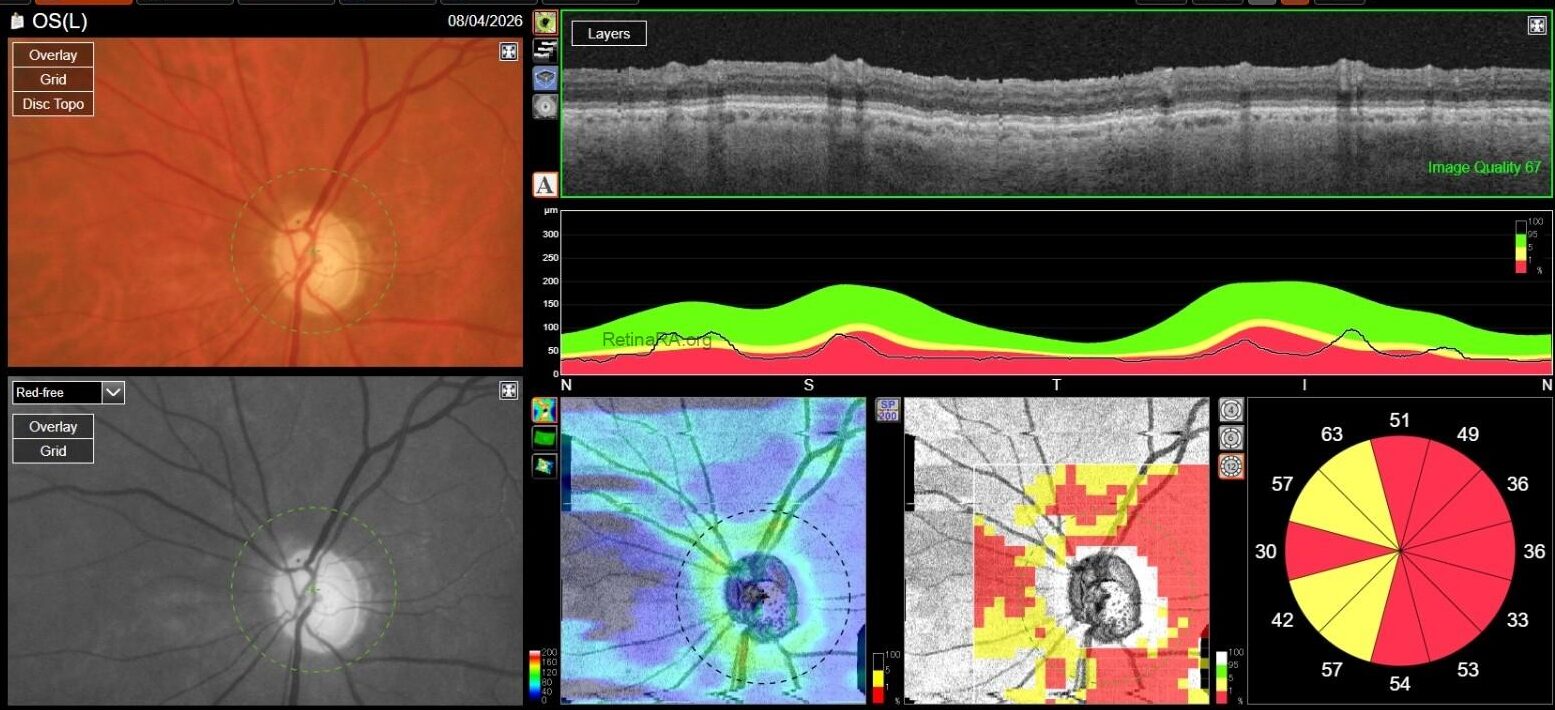

Optic Disc OCT with RNFL thickness quantification was performed as well; while in OD it revealed a minimal RNFL defect, in OS it showed extensive and severe RNFL thinning in all sectors, which was also confirmed on GCL+/GCL++ analysis by means of a 3D macula scan.